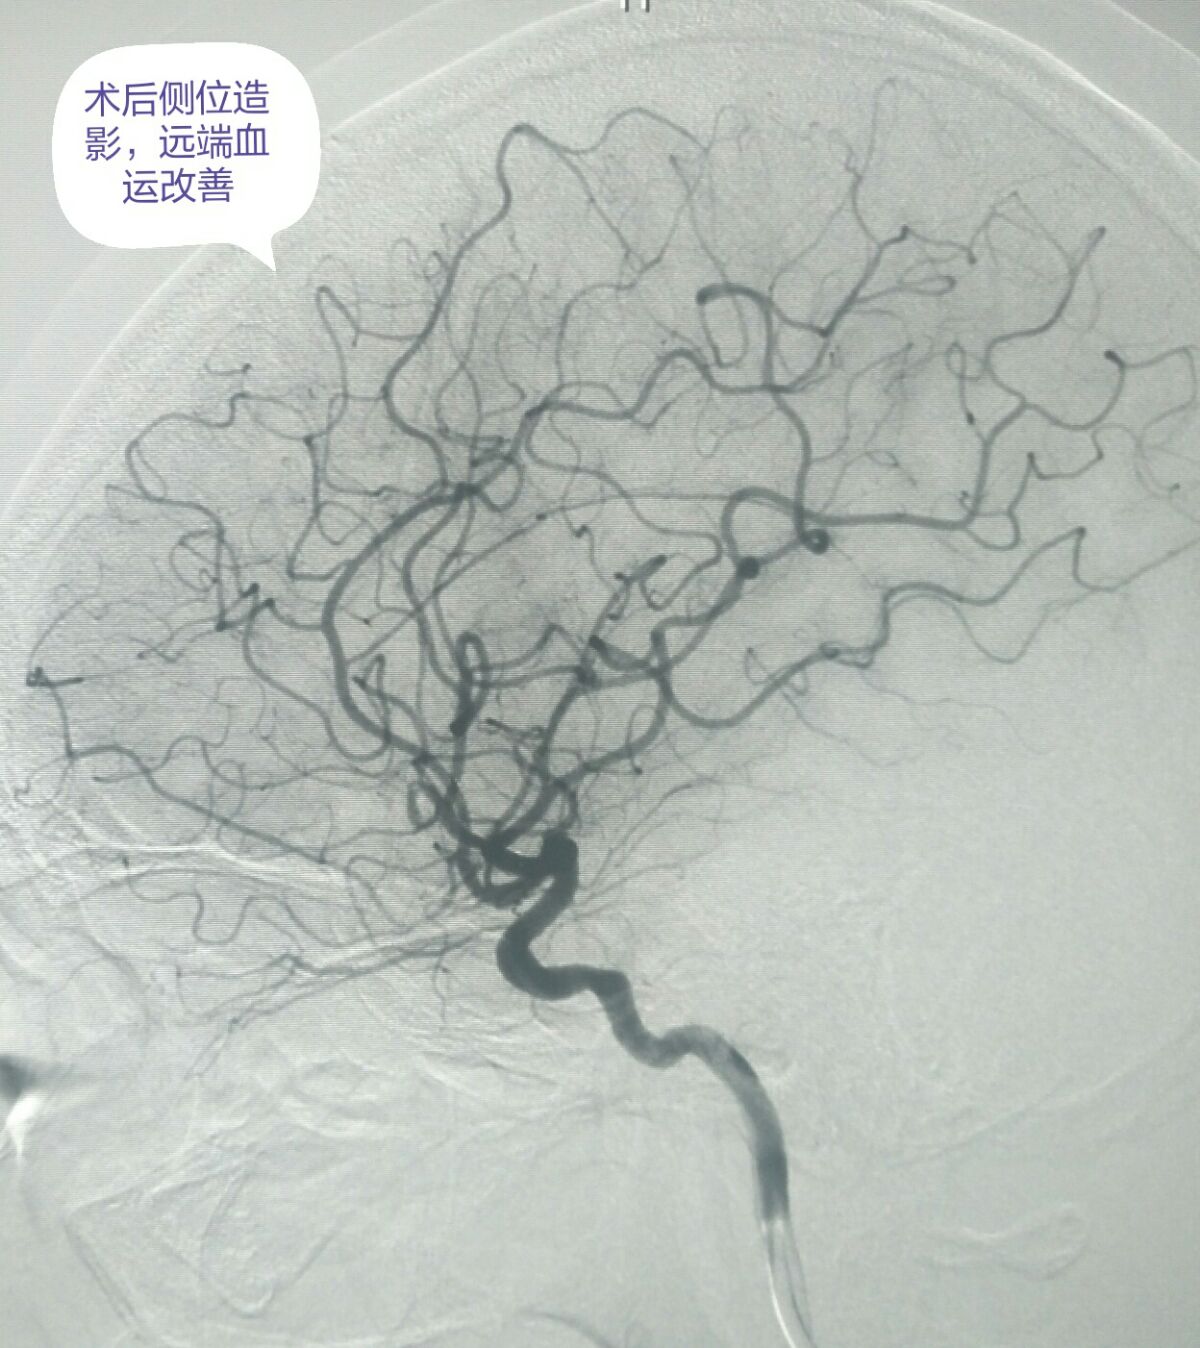

侧位造影显示血管形态良好,远端血流明显改善